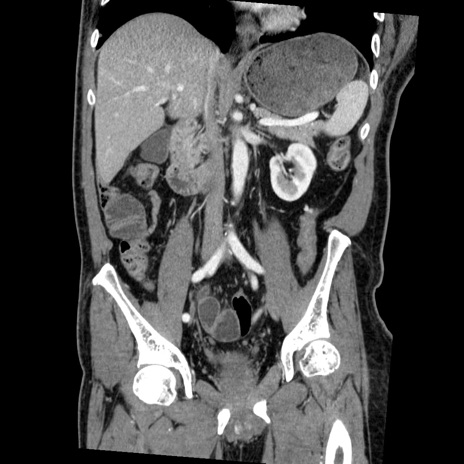

症例22(冠状断像)

【症例】50歳代男性

【主訴】腹痛

【現病歴】AVMからの被殻出血のため回復期リハ病棟入院中。 本日午後3時頃急に下腹部痛が出現した。

【既往歴】AVM、被殻出血、虫垂炎、高血圧

【身体所見】意識晴明、左半身不全麻痺、会話の理解は良好、36.5°C、腹部:膨隆、全体に板状硬、下腹部正中に圧痛点あり、反跳痛-、筋性防御不明、右下腹部にope scar

【データ】WBC 9400、CRP 0.06